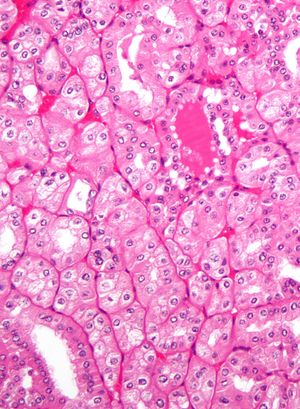

신세포암(신장암, 그라비츠 종양)은 신장의 요세관 상피세포의 선암이다. 반복되는 육안적 혈뇨가 관찰되며, 이를 간헐적 육안적 혈뇨라고 한다. 신혈관을 압박하여 신혈관성 고혈압을 나타내는 경우도 있다. 남녀 비율은 3:1이며, 간헐적 혈뇨는 약 50%에서 관찰된다. 신세포암은 독일의 병리학자 그라비츠(Grawitz)에 의해 자세히 설명되었다.

신장 악성 종양 중 가장 흔한 유형은 신세포암[34]이며, 네프론의 근위세뇨관 세포에서 기원하는 것으로 여겨진다.[15][35] 신세포암은 조직학적 특징과 유전적 이상을 기반으로 하위 유형으로 더 세분화되었다. 2004년 WHO 성인 신장 종양 분류는 다음과 같다.[40]